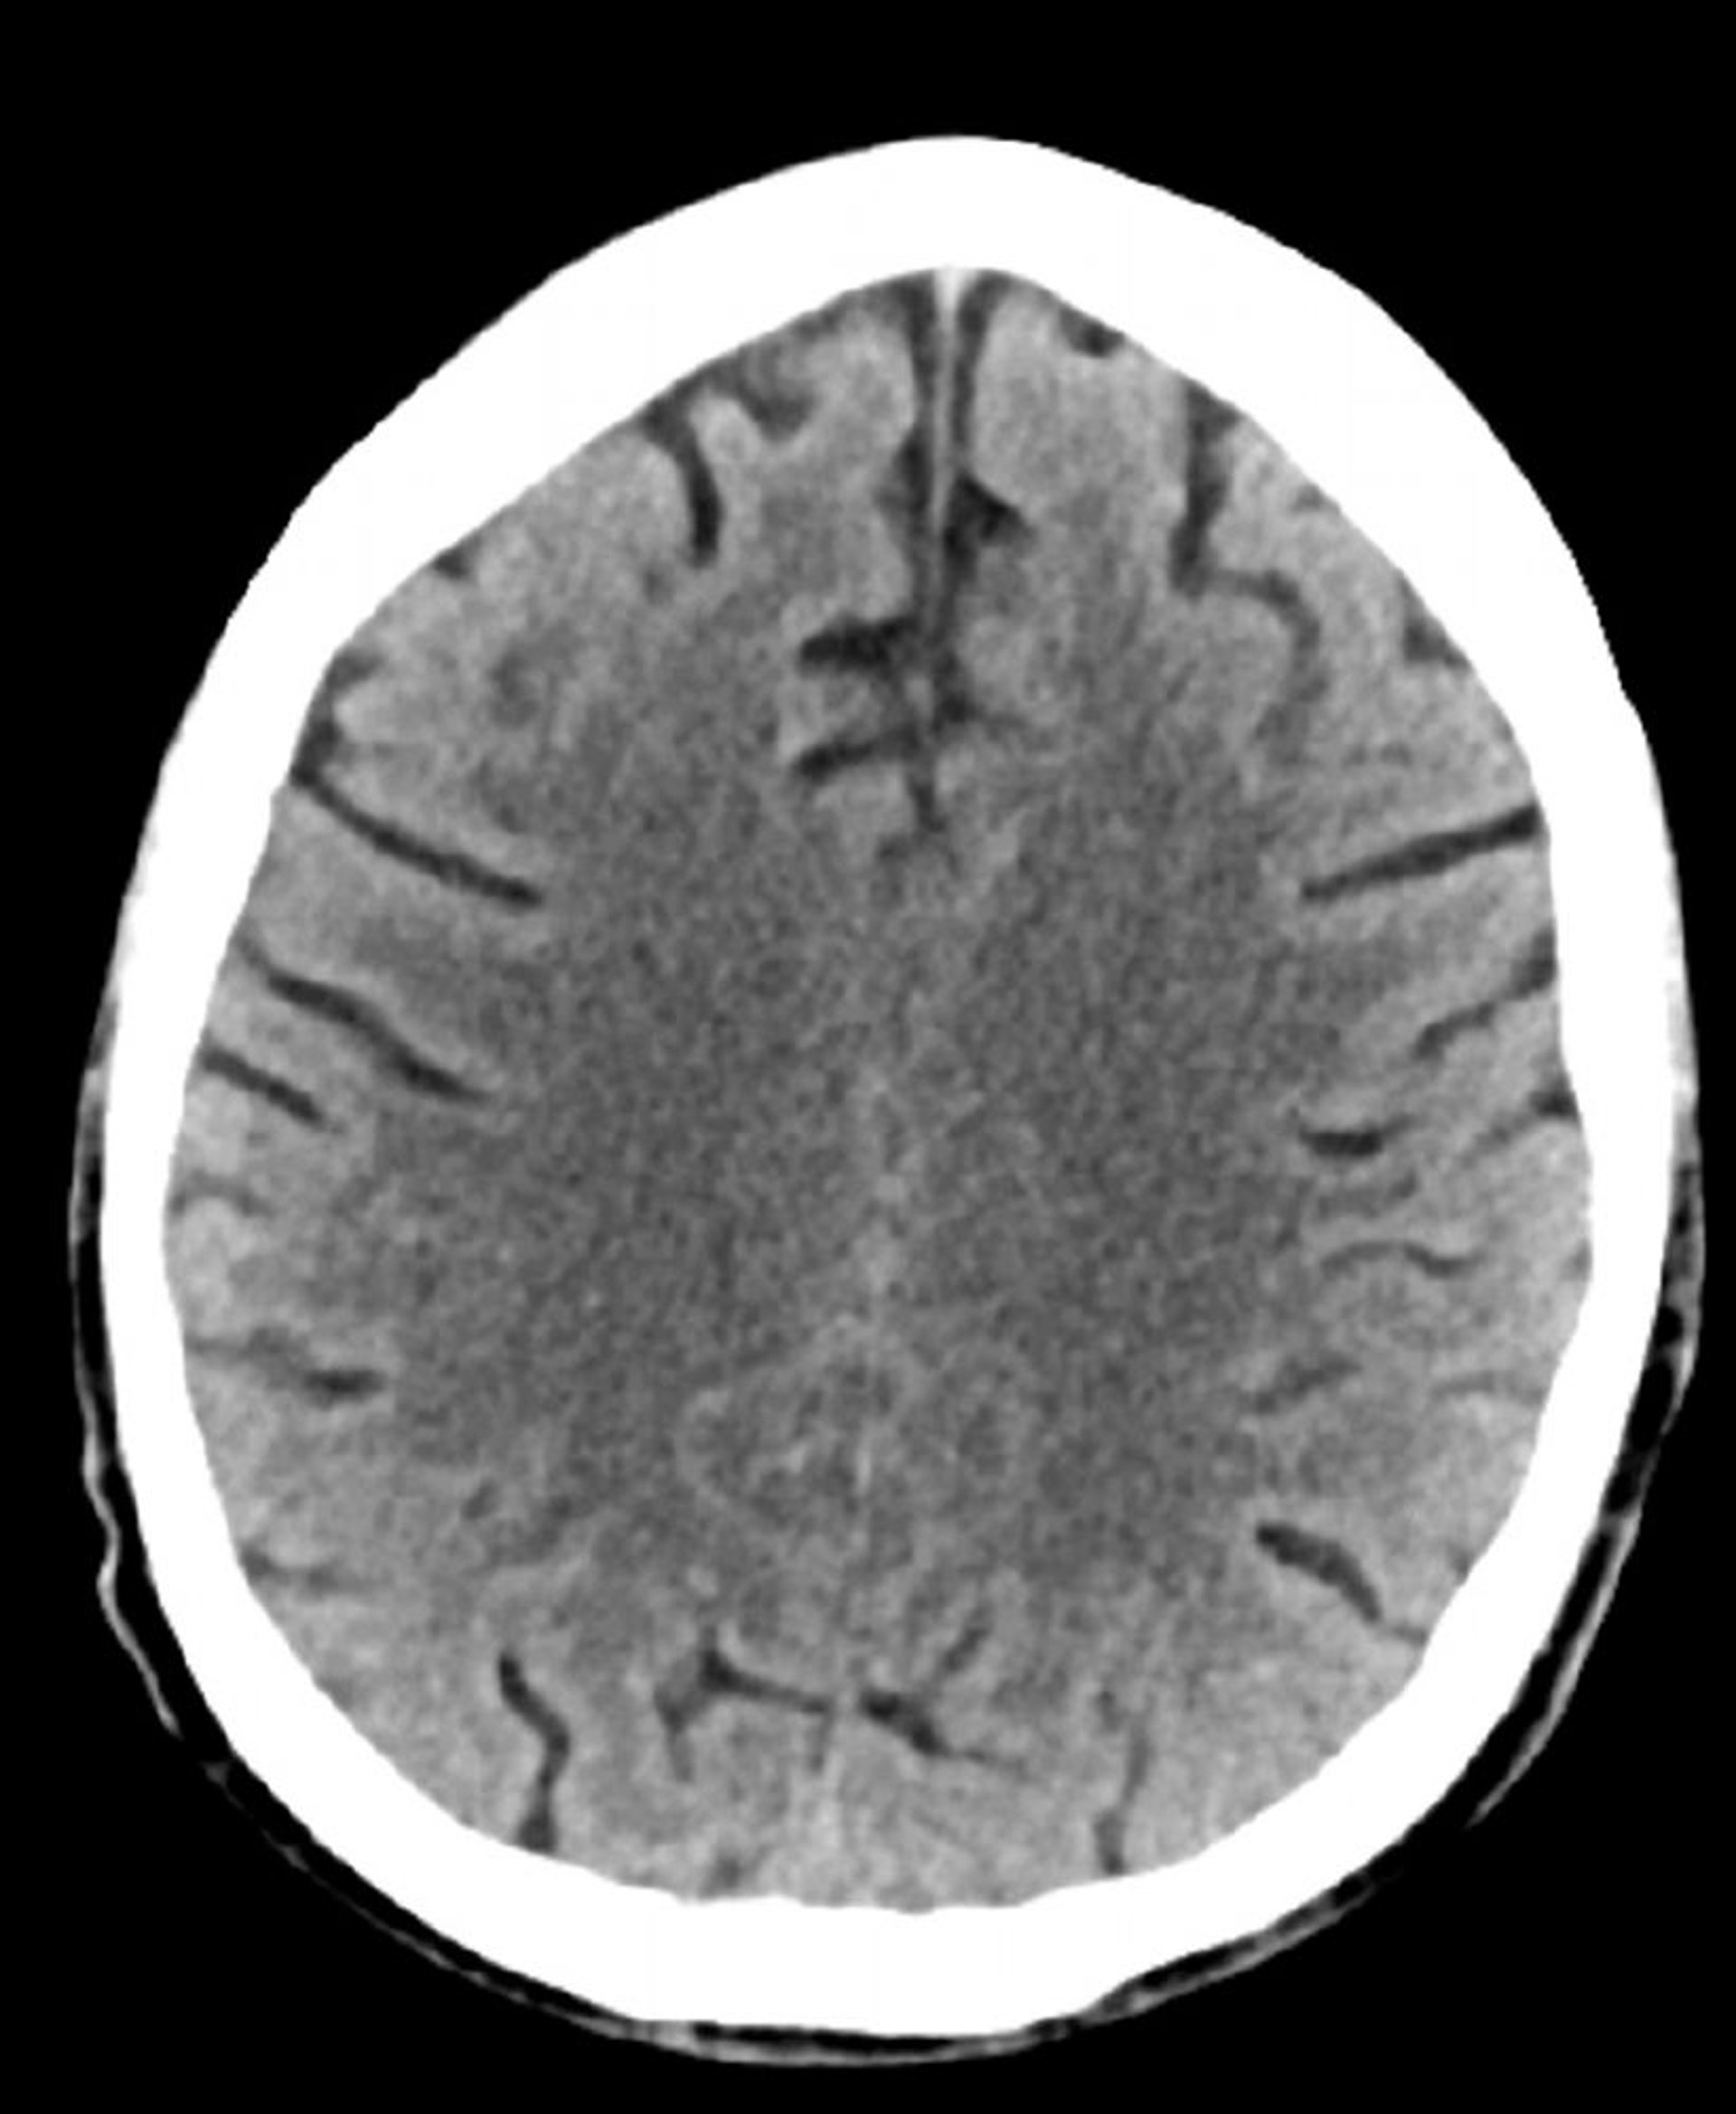

Normaler Kopf CT-Scan (Erwachsene, Alter 74) – Folie 2

Dieses Bild ist ein normaler CT-Scan des Kopfes eines Erwachsenen im Alter von 74 Jahren. Im Vergleich zu einer normalen CT-Aufnahme des Kopfes eines 30-Jährigen sind die Sulci größer. Diese Ergebnisse sind in dieser Altersgruppe normal.